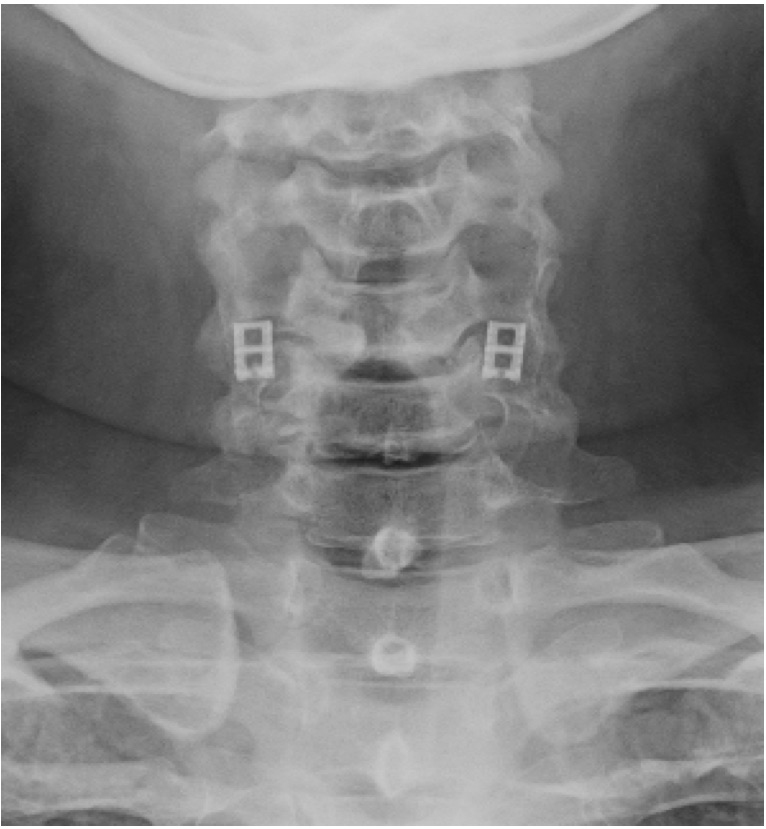

El sistema DTRAX® se compone de 2 cuñas de titanio que se introducen entre las facetas articulares cervicales para conseguir un aumento del espacio foraminal produciendo así la descompresión de la raíz o raíces nerviosas comprimidas a través de la distracción facetaria a la vez que produce una fijación estable de la articulación en el nivel implantado favoreciendo la fusión. Todo ello se realiza mediante un abordaje mínimamente invasivo gracias a un instrumental especialmente diseñado para ello.

DTRAX® está indicado para su uso en pacientes esqueléticamente maduros con patología degenerativa discal de la columna cervical (C3 a C7) con acompañamiento de radiculopatía y/o dolor facetario. La distracción facetaria que produce el DTRAX® hace que el espacio foraminal aumente aproximadamente en un 20% además de producir una estabilización de la articulación mayor en movimientos de rotación axial y movimientos laterales e igual en flexo- extensión si lo comparamos con la estabilización que produce una caja y una placa colocada mediante un abordaje anterior tradicional.